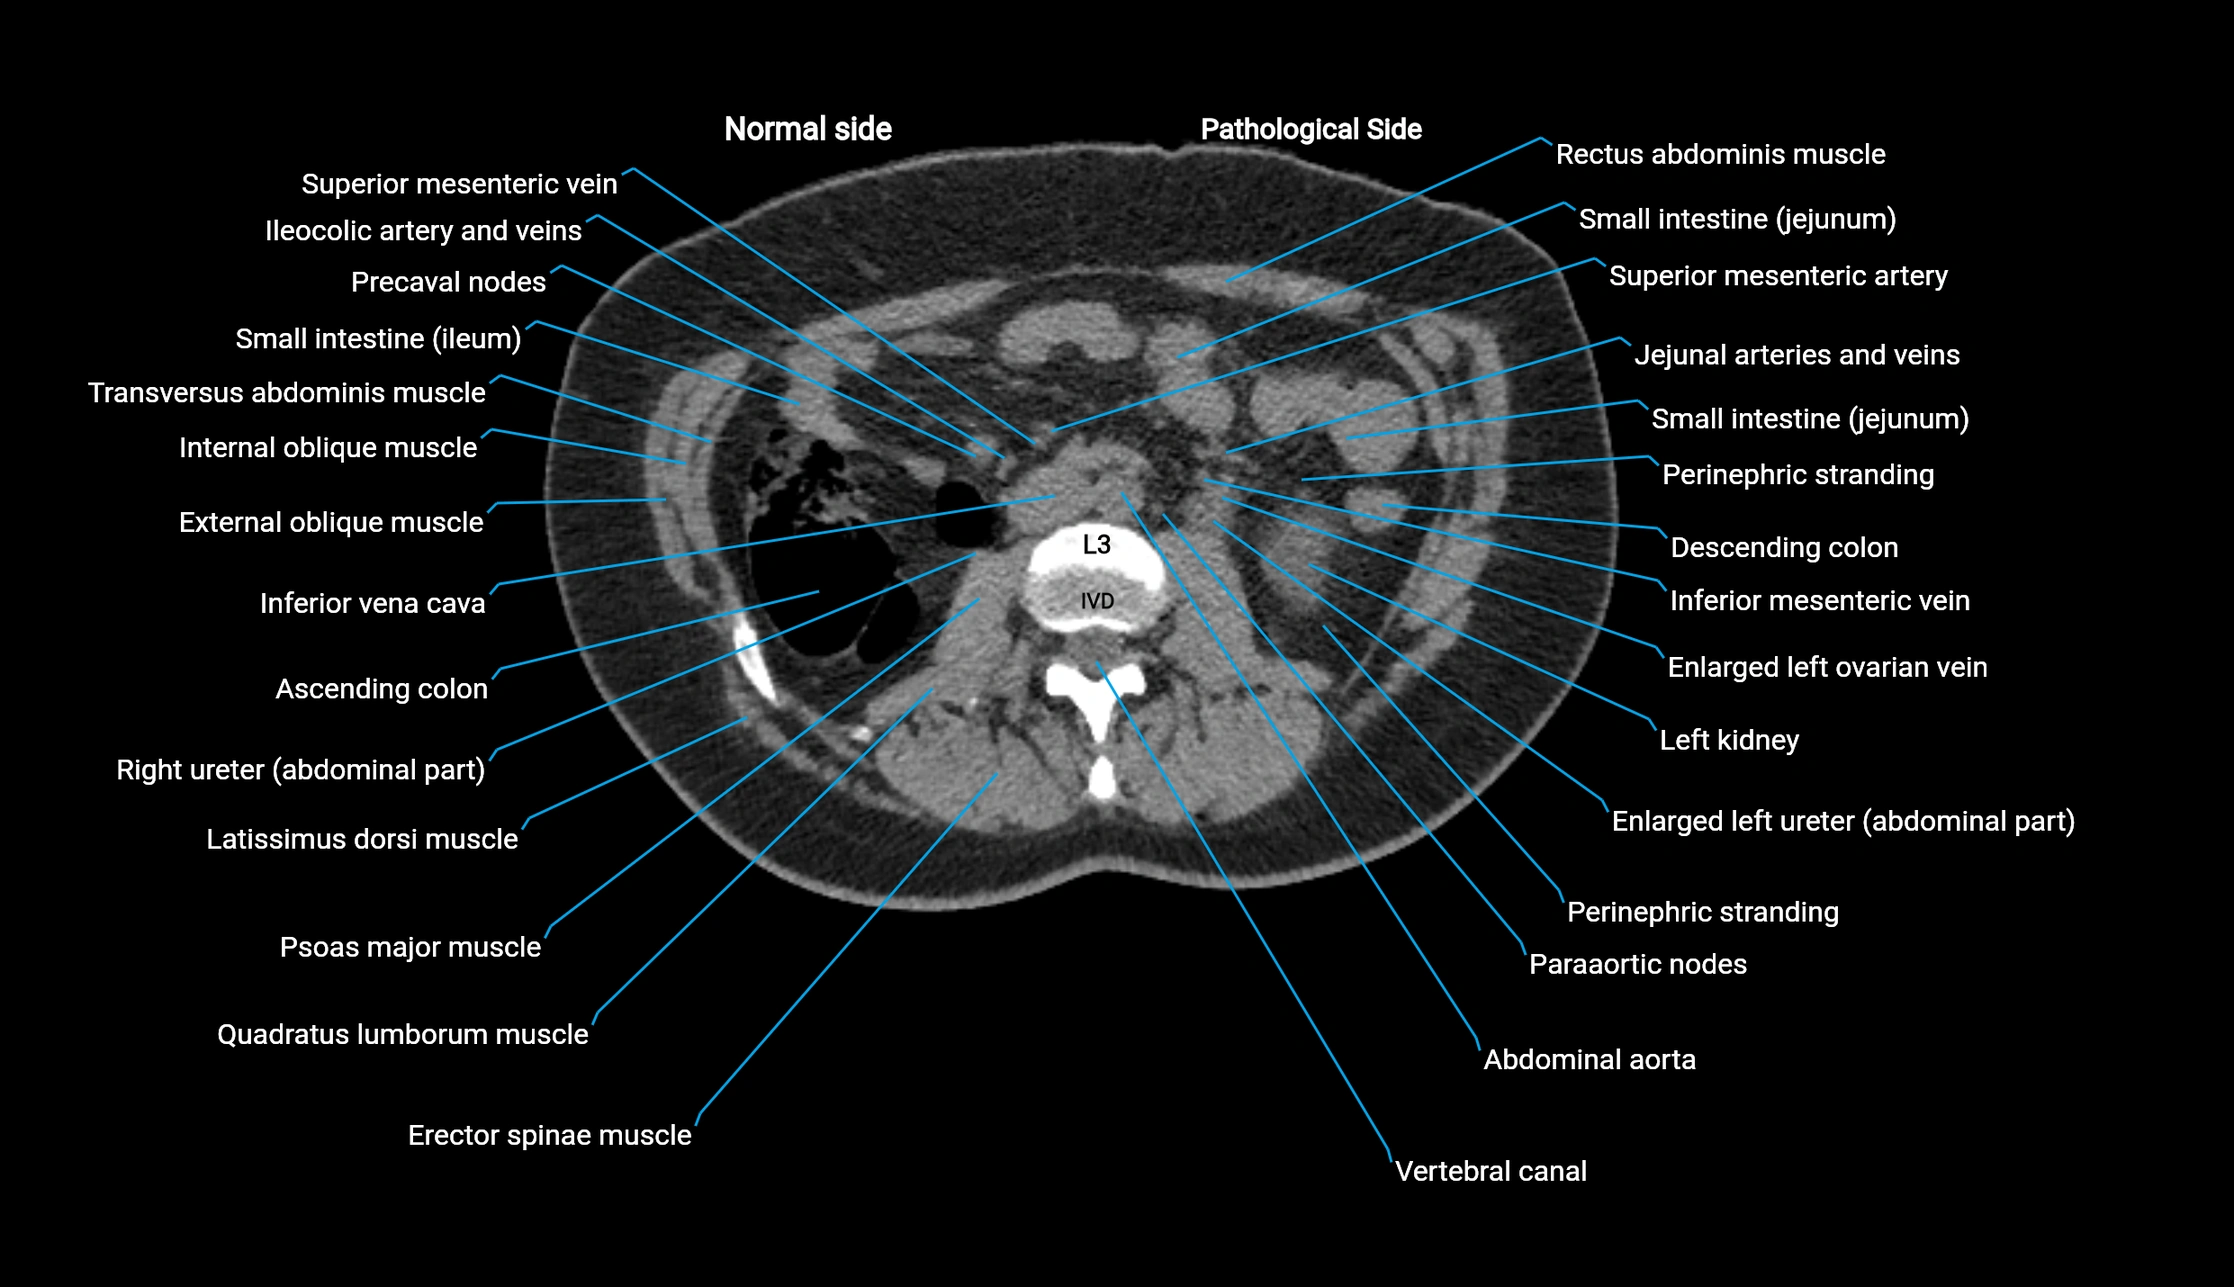

CT VRT 3D image

image